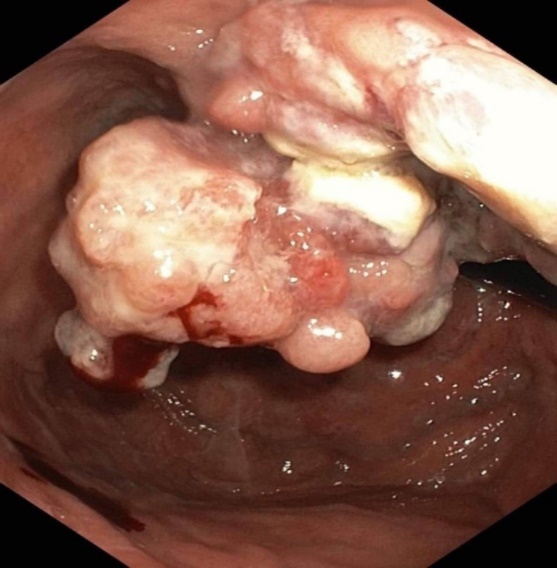

The polypoid type of gastric cancer was observed in 3 (4,9±2,8%) cases, the ulcerative type – in 18 (29,5±5,8%), the infiltrative ulcerative type – in 27 (44,3±6,4%) and the diffuse infiltrative type – in 13 (21,3%±5,2%) cases respectively (Table 2). On the echogram, the tumor was

Visualized as a polypoid formation on a wide base above the gastric mucosa of a non-uniform structure, an irregular surface (Figure 5, Figure 6, Figure 7).

Figure 6.The gastric carcinoma for T3 stage. The tumor is visualized as a polypoid formation on a wide base above the gastric mucosa of a non-uniform structure, an irregular surface (arrows).

Figure 7.Endoscopic picture of gastric carcinoma for T3 stage. The tumor is visualized as a formation on a wide base above the gastric mucosa of a non-uniform structure, an irregular surface (arrows).